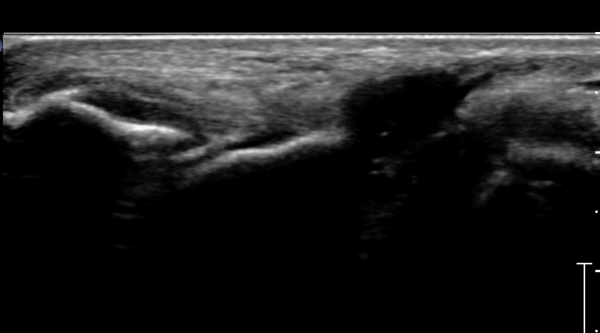

ÃÊÀ½ÆÄ°Ë»ç : ¹ß¸ñ °üÀý Á¾´Ü¸é°Ë»ç¿¡¼­ ¹ß¸ñ °Å°ñ ¿¬°ñÀÌ ¾ã¾îÁ®(thinning) º¸ÀδÙ(»çÁø 1).